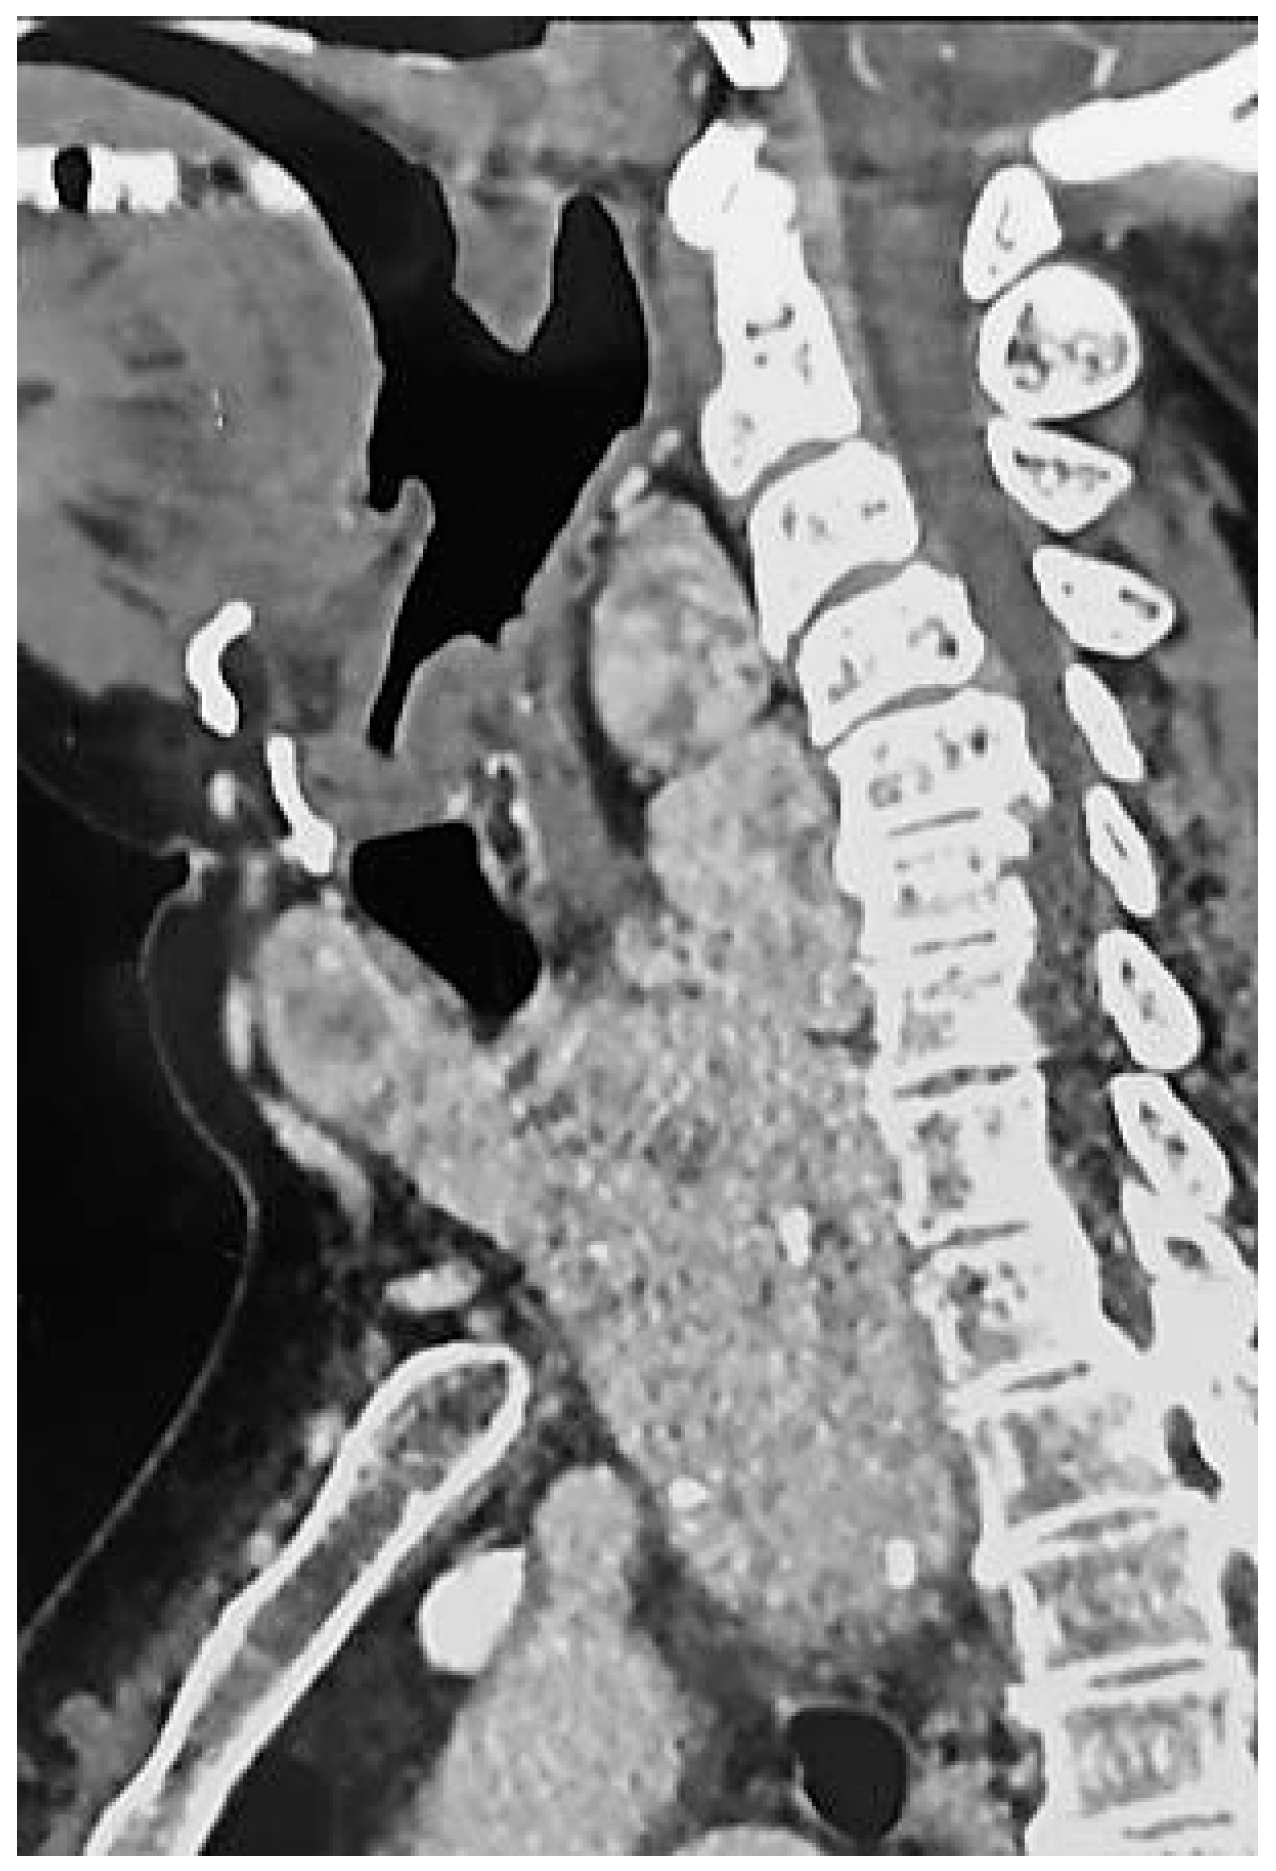

The Resolution of Obstructive Sleep Apnea in a Patient with Goiter after Total Thyroidectomy: A Case Report

2. Case Description